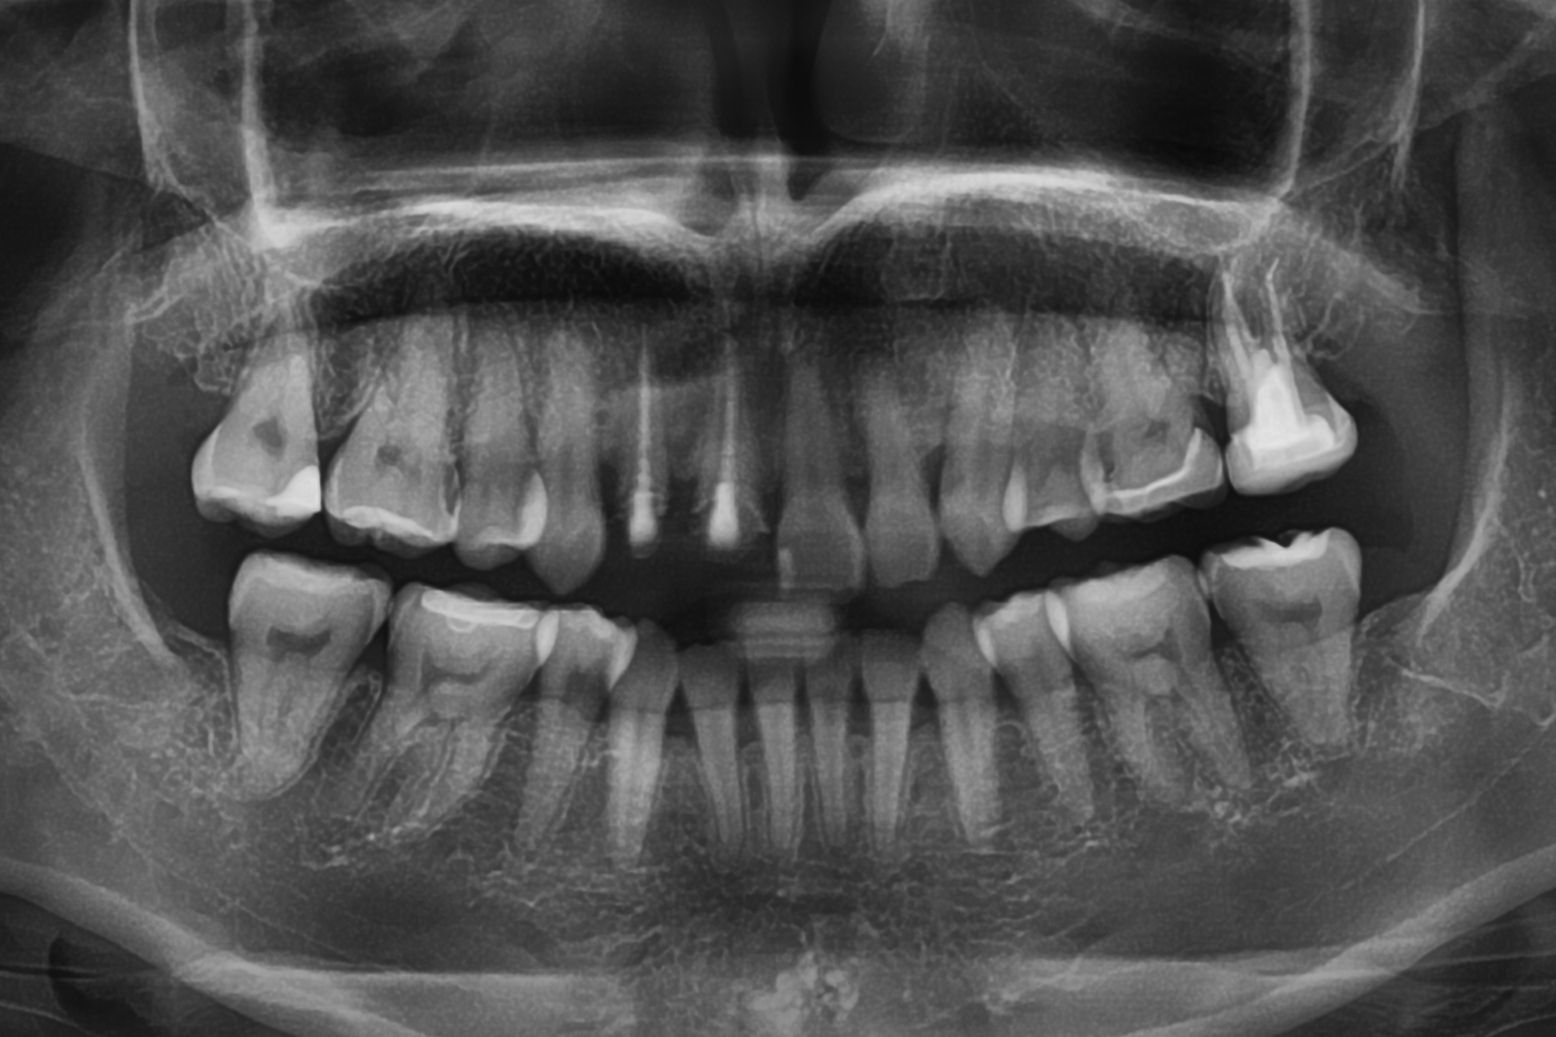

親知らずの周りには、重要な血管や神経が通っています。抜歯の際には、それらを傷つけないよう細心の注意が必要になります。

そのため「CT」で撮影することで、親知らず付近の血管や神経の位置を詳細に把握できます。これは安全な抜歯のために欠かせない、大切な検査といえます。

ほかの歯科医院では、大学病院などに紹介されるケースの場合でも、当院で柔軟に対応可能です。ただし、「心臓病」「重度の糖尿病」「神経や血管を損傷するリスクが高い」といったケースでは、ほかの病院を紹介させていただく場合もあります。